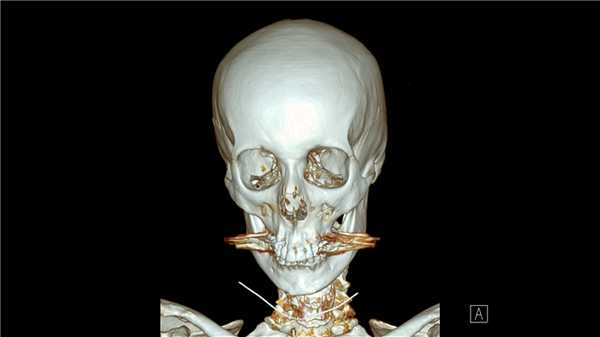

КТ при переломах

Компьютерная томография (КТ, или МСКТ) является наиболее информативным методом визуальной оценки посттравматических изменений костей, суставов и окружающих тканей. В отличие от других видов лучевой диагностики, при КТ тело человека сканируется поперечно тонкими срезами, на сканах визуализируются ткани различной морфологической структуры (кости, внутренние органы, системы кровообращения и лимфотока), а на основании полученных изображений создается трехмерная модель-реконструкция исследуемой части тела и сканы в трех плоскостях.

Таким образом, будучи пространственным, а не плоскостным (как рентген) методом визуализации любых костных анатомических структур, КТ позволяет достоверно определить тип травмы, увидеть возможные осложнения и повреждения соседних тканей. Поэтому среди врачей это исследование считается предпочтительным для диагностики переломов, особенно осложненных, в том числе внутрисуставных, не рутинных. Плюсом КТ также является оперативность и простота обследования для пациента.

Компьютерная томография позволяет детально визуализировать кости, суставы и окружающие ткани в режиме 3D, что делает этот метод идеальным для диагностики переломов разной степени сложности. Врач-рентгенолог увидит даже небольшое смещение костей, сколы и трещины, а также сможет точно рассчитать любые отклонения с помощью программного обеспечения. На трехмерной реконструкции отсутствуют артефакты (искажения), так что врач сможет точно и достоверно описать результат в заключении.